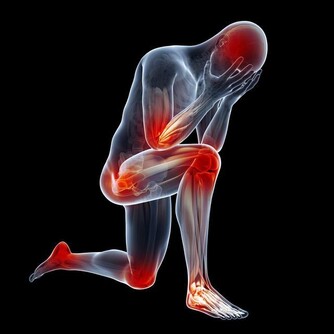

15個信號提醒你要養肝

很多朋友不知怎樣檢測肝臟健康,因為肝臟沒有痛覺神經,很難發現其有不適的症狀。

其實肝臟會通過一些症狀告訴你,它不舒服。以下15個症狀,您可以好好測一下!

1.無端感到疲倦。

2.無端感到煩躁、焦慮和憂鬱。

3.眼睛乾澀或者死魚眼。

4.出現粘便。

5.腰部贅肉增加。

6.有體臭。

7.失眠多夢。

8.口乾口苦。

9.偏頭痛。

10.前胸後背有紅痣。

11.指甲有明顯豎條紋。

12.頭髮經常很油。

13.臉龐兩邊有肝斑。

14.脾氣特別大。

15.乳腺增生和婦科問題。